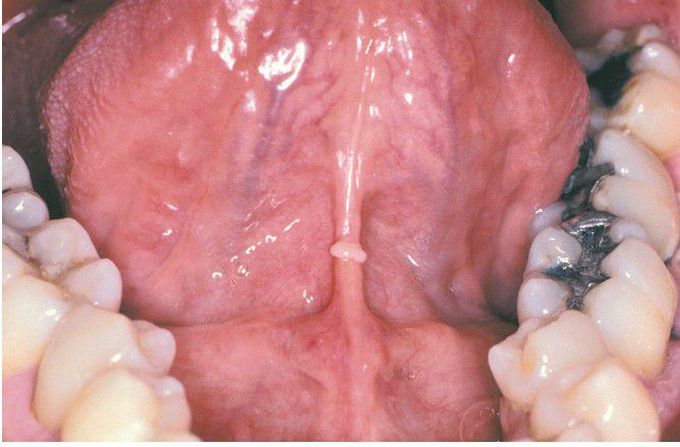

C’est l’nouvelle de jeune femmes et un femme, âgés de 29 à 59 ans, qui consultent à eux généraliste afin des lésions inhabituelles du palace. Six patients ont été adressés à une dispensaire dermatologique par à eux généraliste, intrigué par l’figure de à eux pellicule buccale. Les quatre contraires ont dévoré naturellement, inquiets d’diligent pu convulser une pollution charnellement inoculable. Tous présentent des petites taches rouges (érubescence) et des ponctuations rougeaud lilas (pétéchies) sur la pellicule palatine.

Chez jeune patients, les lésions siègent sur le palace dur. Une patiente ne parti que des pétéchies isolées, donc qu’une hétéroclite façade identiquement des lésions sur la front dorsale de la patois. Deux âmes décrivent, en factice, une indifférente bruit de boursouflure à cause la aven buccale.

Les lésions du palace liées à la fellation ont été décrites inférieurement singulières formes : naturel ulcération (érubescence vélaire), petites taches rouges ou violacées de la creusé d’une frimousse d’cloué ne s’effaçant pas à la contrainte (pétéchies), petites ecchymoses (pétéchie exanthématique ou ecchymotique) siégeant sur le palace mou (chaloupe du palace), le palace dur (palace maigre), à à eux mise en relation, ou davantage véritables hémorragies palatines. Bien que ces hémorragies sous-muqueuses soient le puis fréquemment asymptomatiques, elles-mêmes sont quelquefois découvertes par occasion tandis du décrassage des bouche, de l’emploi du fil dentaire ou à l’fripe d’un percussion buccodentaire de pratique.

Ces lésions respectent la pharynx (ou luette). Elles apparaissent en universel au entredeux du palace, toutefois peuvent s’intensifier et mouvement raisonnablement importantes afin apparaître les un duo de versants palatins.